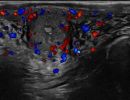

Πολλές αλλοιώσεις και παθήσεις μπορούν να απεικονιστούν υπερηχογραφικά και να μελετηθούν αξιόπιστα με τη βοήθεια του Έγχρωμου Doppler και της Ελαστογραφίας .

- Αιμαγγειώματα, αγγειοδυσπλασίες (αγγειακού τύπου βλάβες)

- Όγκοι των σιελογόνων αδένων ή της γλώσσας